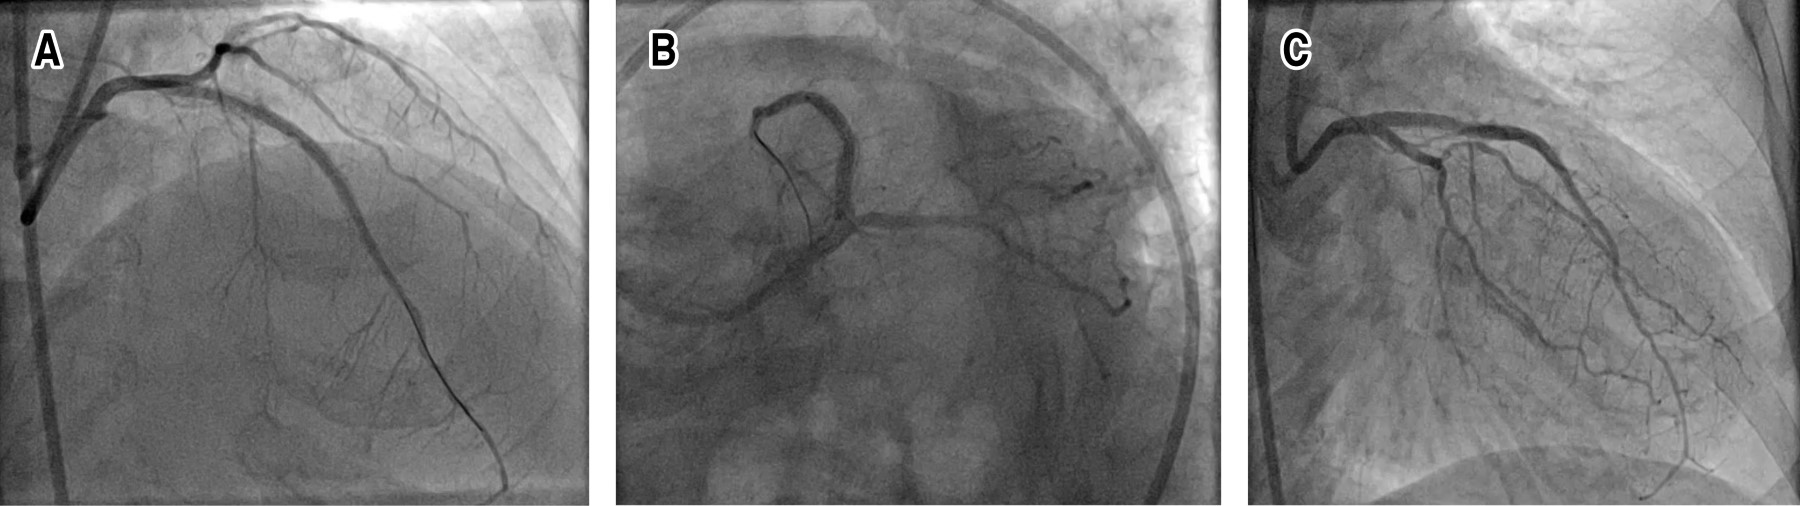

La subexpansión es una cuestión importante para los cardiólogos intervencionistas en términos de resultados a largo plazo. En este documento informamos una rotación exitosa de puntales de stent subutilizados. Mujer de 75 años con antecedentes de Intervención Coronaria Percutánea (ICP) sobre Arteria Descendente Anterior (ADA) izquierda con dos stents farmacoactivos superpuestos hace una semana en otro centro. Desafortunadamente los stents se desplegaron sin una preparación adecuada de la lesión en lesiones muy calcificadas y por lo tanto, no se pudieron dilatar adecuadamente después del despliegue. Los struts de la endoprótesis se rotaablizaron con éxito con fresas de 1.5 y 1.75 respectivamente y a continuación se implantó la endoprótesis. El paciente fue dado de alta sin incidentes. La expansión insuficiente de un stent generalmente se debe a una preparación inadecuada de la lesión. El deterioro de la cicatrización secundario a puntales del stent poco expandidos es la principal causa de reestenosis a corto plazo. Por lo tanto, es de gran importancia una predilatación adecuada, especialmente en lesiones muy calcificadas. Se deben utilizar técnicas más sofisticadas como balón Non-Compliant Balloon (OPN), rotablación, balón de ondas de choque y láser para una predilatación adecuada cuando los métodos convencionales de predilatación con balón fallan. Estos métodos también se pueden utilizar para la dilatación de un stent poco expandido. En consecuencia, la expansión insuficiente de un stent es una de las principales causas de reestenosis del stent. La rotaablación se puede utilizar para reducir el tamaño de los puntales del stent poco expandidos y por lo tanto, prevenir una posible reestenosis a corto plazo.

Figura 2